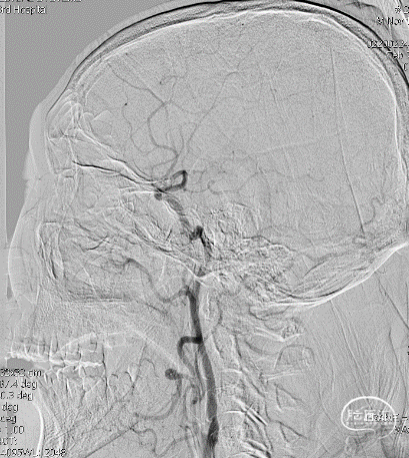

局麻,右股动脉入路置8F短鞘,导管导丝技术将8F MPA置于右C1末端,造影确认右M1急性闭塞,侧支代偿差。

以Transend导丝 + Headway21导管到达M1中段,Sofia PLUS顺畅到位(M1中段),ADATP技术抽吸取栓,一次成功取通,前向血流恢复至TICI3级,无栓子逃逸及原位狭窄,穿刺至开通时间20min(患者术中间断躁动不配合)。

开通右MCA后,行左侧颈动脉及左椎动脉造影显示血流通畅(双侧后交通动脉开放)。

右颈动脉再次造影见前向血流持续通畅,患者此时左侧下肢肌力恢复Ⅲ级、上肢Ⅰ级、语言功能好转,遂结束手术。

以Sofia Plus进行抽吸取栓1次(ADAPT技术),实现血流复通(TICI 3级)